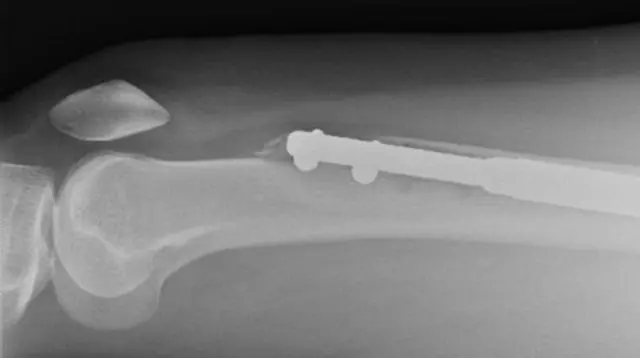

ኣብዚ ኣገባብ ሕክምና ቃንዛ ትጽቢት ዝግበረሉ እዩ። ኣብ እዋን’ቲ መጥባሕቲ ኣዕጽምቲ እግሪ ኣብ ክልተ ተሰቢሩ ኣብ ውሽጡ ሓፂን ይግጠም።

እቶም ብሓጺን ዝተሰርሑ ነኣሽቱ ነገራት ነቲ ኣብ ክልተ ዝተሰበረ ዓጽሚ ንምፍላይ በብቑሩብ ይዝርግሑ። እዚ መስርሕ’ዚ ቁመት ናይቲ ተሓካሚ ንምዕባይ ዝዓለመ’ዩ። እቶም ዝተሰብሩ ኣዕጽምቲ ኣብ መንጎ ዘሎ ሃጓፍ ንምምላእ በብቑሩብ ተመሊሶም ክሓውዩ ኣለዎም።

ኢሌን ስካን ክትገብር ምስከደት ዝፈርሐቶ ነገር ከምዘጋጠመ ኣረጋገጸት። እቲ ኣብ ጸጋመይቲ እግራ ዝተገጠመ ሓጺን ነቲ ኣብ ኣካላት ወዲ ሰብ ዝጠንከረ ዓጽሚ ከምዝሰበሮ ፈለጠት። ንሳ ክትጭነቕ ከላ ሓኪማ ዶክተር ጉይሸት ግን መረጋገጺ ከምዝተወሃባ ትዛረብ።

ድሕሪ ሽዱሽተ ሰሙን ኣብ የማነይቲ እግራ ዝተገብረ ስካን ዘሰክፍ ጸገም ዕብየት ዓጽሚ ኣርእዩ። ዓጽሚ እግራ በቲ ብሓጺን ምስተትሓሓዘ ዘይለገበ ነይሩ።

ኢሌን ሓገዝ ንምርካብ ናብ ዶክተር ጉይሰች ምስከደት ናብቲ ኣብ ሚላኖ ዝሰርሓሉ ዝነበረ ክሊኒክ ንካልእ መጥባሕቲ መደብ ኣትሓዛ። ኣብ ሚያዝያ 2017፡ ኣብ ጸጋማይ እግሪ ኢሌን መስርሕ ምንዋሕ ዳግማይ ጀሚሮም። ኣብ የማናይ እግሪ’ውን ዕብየት ዓጽሚ ንምንቕቓሕ ዝሕግዝ ኣንጉዕ ወሰኹሉ። ድሕሪ እቲ መጥባሕቲ ግን ኢሌን ዝያዳ ሕማቕ ዜና ተነገራ።

"ዶክተር ጉይሸት እቲ ሓጺን ኣብ ዘውጽኣሉ ዝነበረ እዋን ከም ዝተሰብረ ነጊሩኒ" ትብል።

“ካብ ካልእ ተሓካሚ ዝተረኸበ ካልእ ሓጺን ከእትወላ ክኢሉ” እዚ ድማ ዝያዳ ገንዘብ ክትኸፍል ከምዝገበራ ወሲኻ ትዛረብ።